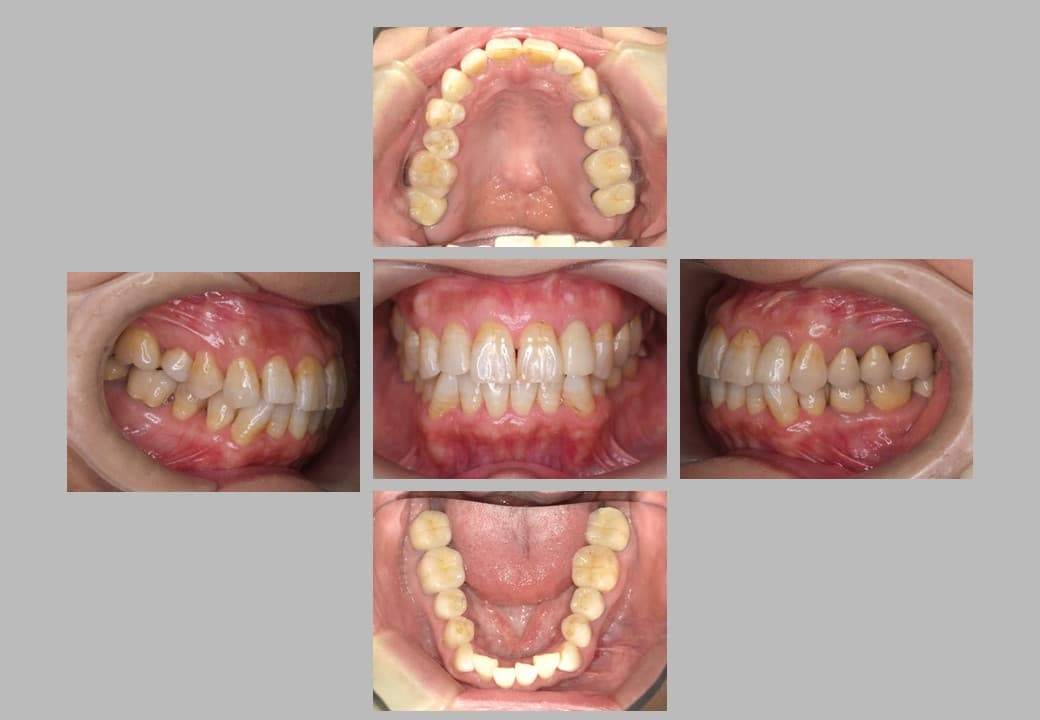

セラミック治療 (メタルフリー治療)の症例紹介②

治療希望:金属の被せ物をセラミックにしたい

治療内容:セラミック治療

治療期間:約6ヶ月

治療前

セラミック治療の実施事例です。